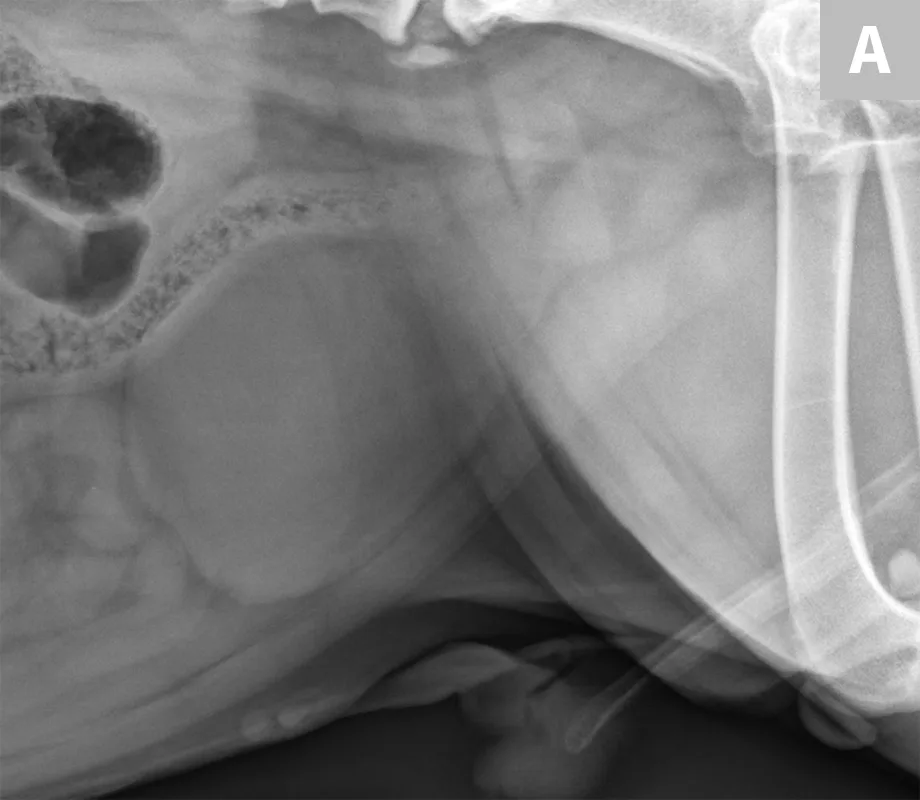

Clinical signs associated with ureteral calculi may range from chronic non-specific signs to acute or chronic renal failure. The presence of hydronephrosis can be highly suggestive of a ureteral obstruction (Figure 6).

FIGURE 6A

Mild to moderate right hydronephrosis and proximal ureteral dilation in a Dalmatian.

Differentiation between a complete vs partial ureteral obstruction can be difficult with survey radiography and ultrasonography alone. Antegrade pyelography (nephropyelocentesis with renal pelvic injection of iodinated positive contrast medium using ultrasound guidance) may be useful for documenting a complete vs partial obstruction (Figure 7).11